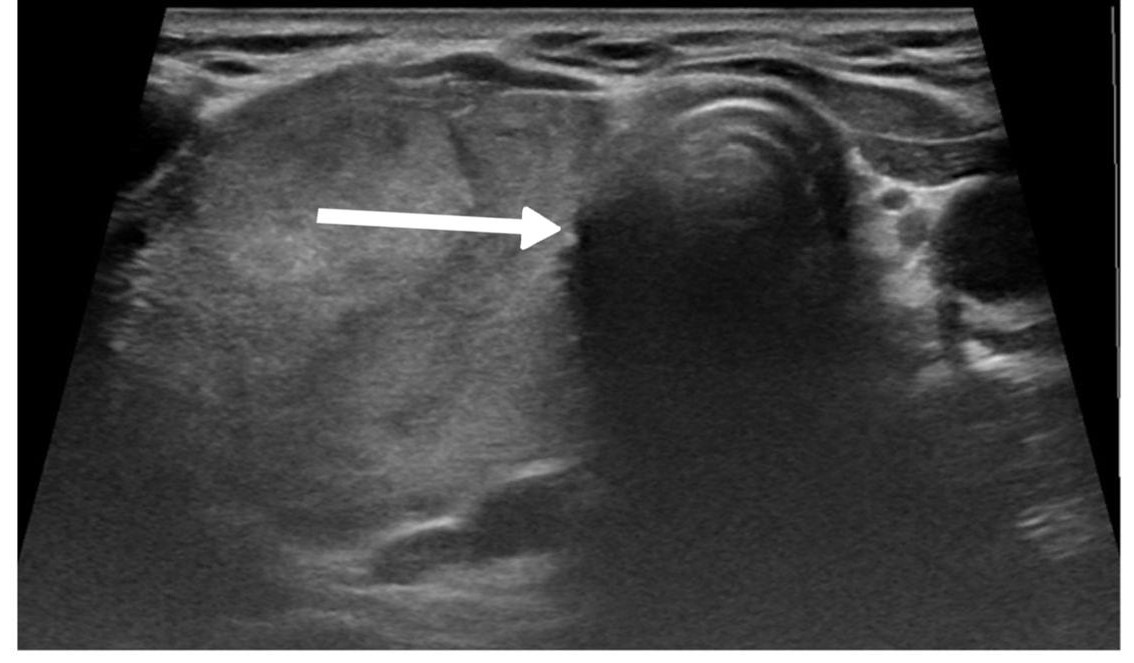

The left thyroid lobe was involved in five cases (45.5%), the right lobe in four cases (36.4%), and the isthmus in two cases (18.1%). The primary surgical approach was total thyroidectomy in seven cases (63.6%), including one patient who underwent concurrent neck dissection (Table 2). Tumor size ranged from 0.5 to 5.5 cm, with a mean size of 2.6 cm (Table 3). All the diagnoses were made post-operatively through histopathological examination (Figure 1).

The diagnostic evaluation of most thyroid nodules typically begins with U/S, followed by fine needle aspiration (FNA). The U/S findings suggestive of HTT are well-defined, solitary, oval or round, solid hypoechoic nodules, usually without microcalcifications and displaying peri or intra-nodular vascularity. However, these features are not specific to HTT and may also occur in other thyroid lesions [7]. Recognizing the variability in U/S findings is crucial, as some studies reported an absence of malignant features. In contrast, Choi et al. found that 29% of HTT cases displayed malignant features on U/S [5,11]. In the present study, five cases were classified as mildly suspicious for malignancy, and three were considered moderately suspicious for malignancy according to the thyroid imaging reporting and data system (TI-RADS). Among the reviewed cases, malignancy was also suspected in four patients based on the U/S findings [2,3,7-10].